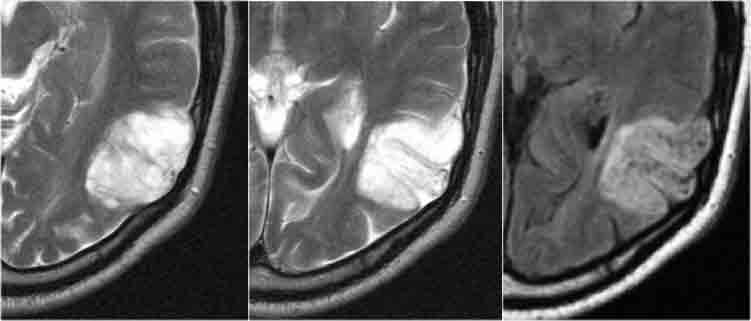

DNET: Chuỗi xung T2W và FLAIR cho thấy hình ảnh bong bóng đặc trưng và phù nề các hồi não bị tổn thương. Lưu ý hình ảnh lõm xương sọ do khối u tăng trưởng chậm.

DNET trong các trường hợp điển hình biểu hiện dưới dạng khối dạng bong bóng làm giãn rộng các hồi não bị tổn thương.

Hình ảnh nang dạng bong bóng được thể hiện bởi các cấu trúc nhỏ giống nang trong khối u, tăng tín hiệu rõ rệt trên chuỗi xung T2W.

DNET ở bé trai 11 tuổi biểu hiện với cơn động kinh cục bộ kháng trị.

Khối u cho thấy hình ảnh dạng bong bóng đặc trưng và có hình ảnh lõm xương sọ kín đáo.